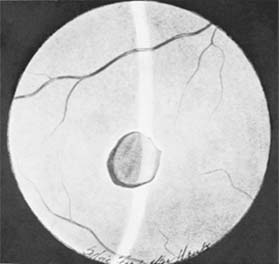

Figure 19-3

Figure 19-3: Hole in retina, macular area, posttraumatic.